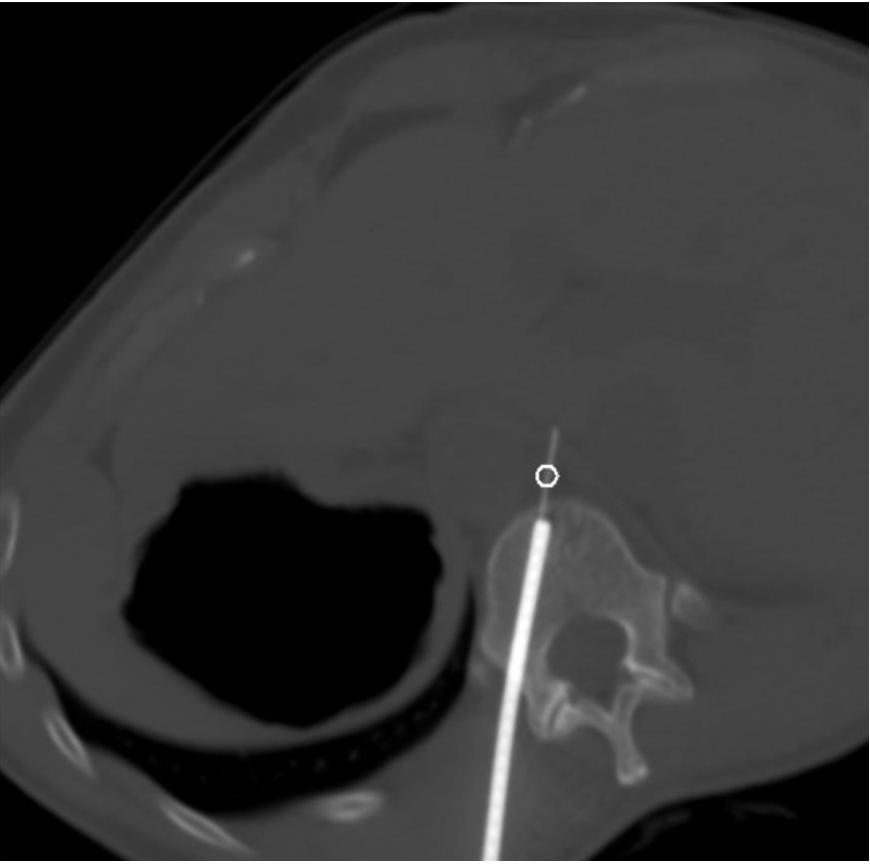

OVERVIEW: A 45-year-old woman was diagnosed with stage IV sigmoid colon adenocarcinoma. She underwent extensive multidisciplinary treatment with chemotherapy and surgical resection including low anterior resection and lymphadenectomy (17/21 lymph nodes positive for metastasis). The following year, her disease recurred, for which she underwent another two surgical para-aortic lymphadenectomies. Despite these aggressive measures, a positron emission tomography/computed tomography (PET/CT) in November 2022 demonstrated a new solitary hypermetabolic right retrocrural lymph node suspicious for metastatic disease. To avoid another surgery for this solitary lesion, she was referred to interventional radiology for biopsy and possible definitive treatment of this solitary site of recurrence.

FIGURE 1. PET/CT with a solitary FDG-avid right retrocrural lymph node. No traditional access for image-guided biopsy and ablation was apparent.